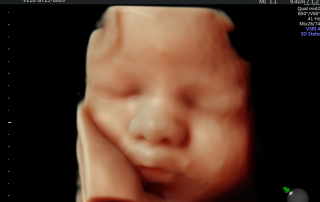

סקירת מערכות

סקירת מערכות אצל מומחה יכולה לזהות עד 90% מהמומים הקיימים בעוברים. מומלץ לקבוע תור מראש על מנת שלא לפספס את חלונות הזמן.